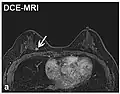

| Dynamic contrast enhanced | DCE | Measures changes over time in the shortening of the spin–lattice relaxation (T1) induced by a gadolinium contrast bolus.[27] | Faster Gd contrast uptake along with other features is suggestive of malignancy (pictured).[28] |

| |